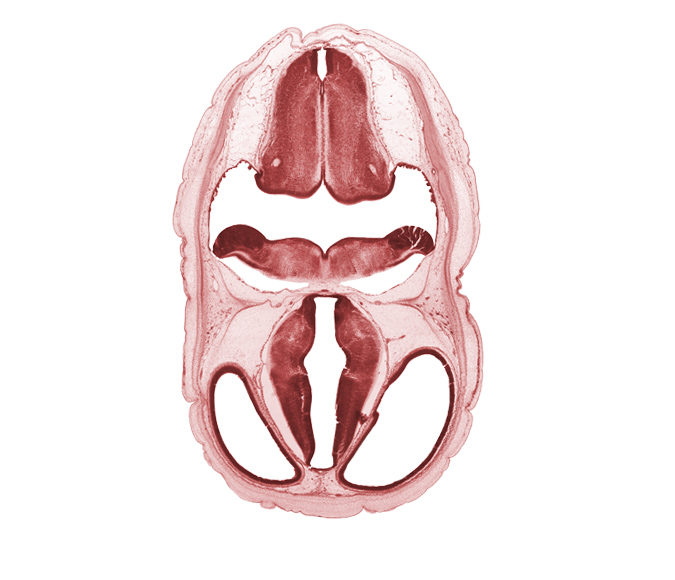

Carnegie Embryo #4090 | Location: 5-15

Keywords: alar plate(s), artifact fracture(s), artifact space(s), basal plate, decussation in floor plate, hypothalamic sulcus, lateral ventricle, obex, posterior communicating artery, rhombencoel (fourth ventricle), sulcus dorsalis, sulcus limitans, third ventricle, venous plexus(es)

Source: The Virtual Human Embryo.